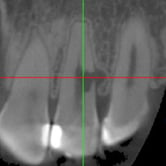

Calcificación Pulpar

La calcificación pulpar es la formación de depósitos de calcio dentro de la pulpa dental, que puede dificultar el tratamiento de conducto.

Los pacientes generalmente no tienen síntomas, pero pueden experimentar sensibilidad.

El tratamiento incluye la eliminación de los depósitos durante el tratamiento de conducto. Es importante tratarlo para evitar complicaciones durante el procedimiento.